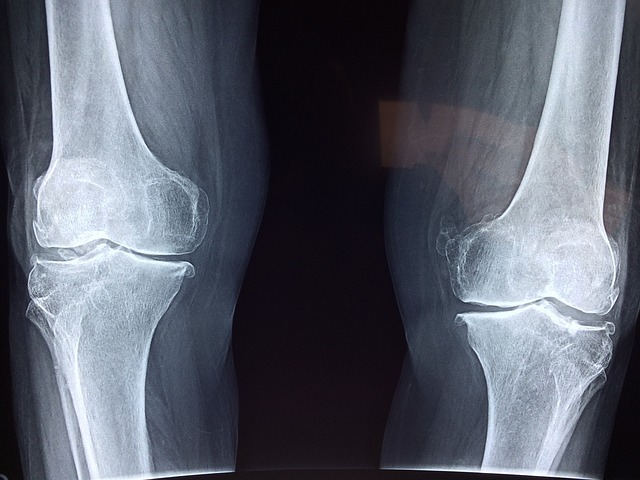

- 관절 통증 및 염증 완화: 옵티머스트에 함유된 성분들은 관절 통증을 완화하고 염증을 줄이는 데 도움을 줍니다. 그루코사민과 콘드로이틴은 연골 조직을 보호하고 재생을 촉진하여 관절 통증을 완화시키는 역할을 합니다.

- 연골 보호 및 재생: 옵티머스트는 연골 조직을 보호하고 재생하는 데 도움을 주는 성분들을 함유하고 있습니다. 그루코사민은 연골 세포의 활동을 촉진하여 손상된 연골을 회복시키고, 콘드로이틴은 연골 조직을 구성하는 단백질 성분으로 연골의 탄력과 강도를 유지합니다.

- 관절 윤활 및 움직임 개선: 옵티머스트는 관절을 윤활시켜 움직임을 원활하게 만드는 역할을 합니다. 그루코사민과 콘드로이틴은 습관성 관절액을 생성하여 관절 표면을 윤활시키고 마찰을 줄여줍니다.

- 관절 건강 유지: 옵티머스트의 성분들은 관절의 건강을 유지하는 데 도움을 줍니다. 그루코사민과 콘드로이틴은 연골 조직의 강도와 탄력을 유지하며, 관절의 안정성을 높여 손상을 예방합니다.

- 뼈 및 연조직 강화: 옵티머스트는 뼈 및 연조직의 강화에도 도움을 줍니다. 그루코사민과 콘드로이틴은 뼈와 연조직의 형성에 필요한 성분으로 작용하여 강력하고 건강한 뼈와 연조직을 유지하는 데 도움을 줍니다.